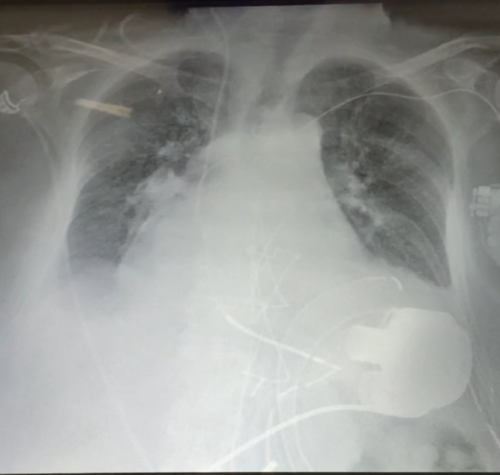

Un cuore artificiale, un sistema di assistenza ventricolare di ultimissima generazione, è stato impiantato con successo al Policlinico di Bari per salvare la vita a un paziente di 65…